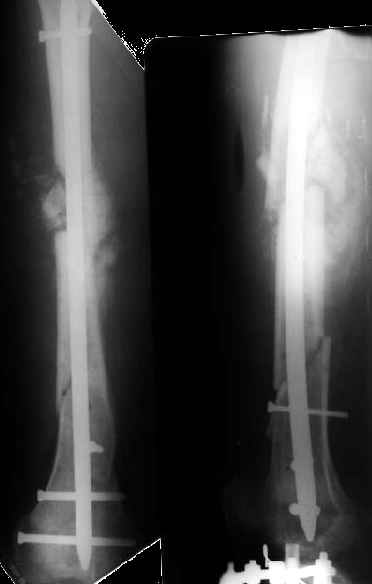

1

2

3

Как я уже сообщал, пациент поступил к нам в пятницу на прошлой неделе.

Ко всему прочему у него еще и разгибательная контрактура коленного сустава - амплитуда градусов 15.

Сегодня сделана операция. Из бедра минимально инвазивно удалены пластинки. Один винт на верхней пластинке оказался сломан, так что пришлось там сделать разрезик побольше, см 5.

Хотя и с трудом, но на бедре удалось сразу выполнить закрытый интрамедуллярный остеосинтез с минимальным рассверливанием.

Редрессацию колена даже пытаться делать не стали.

На голени - чрескожная остеотомия малоберцовой кости, закрытая остеоклазия большеберцовой, дистракционный остеосинтез аппаратом.

В плане - востановление длины и оси голени, разработка движеий в колене. Не уверен, что удастся синтезировать голень стержнем при таком маленьком сгибании в коленном суставе.